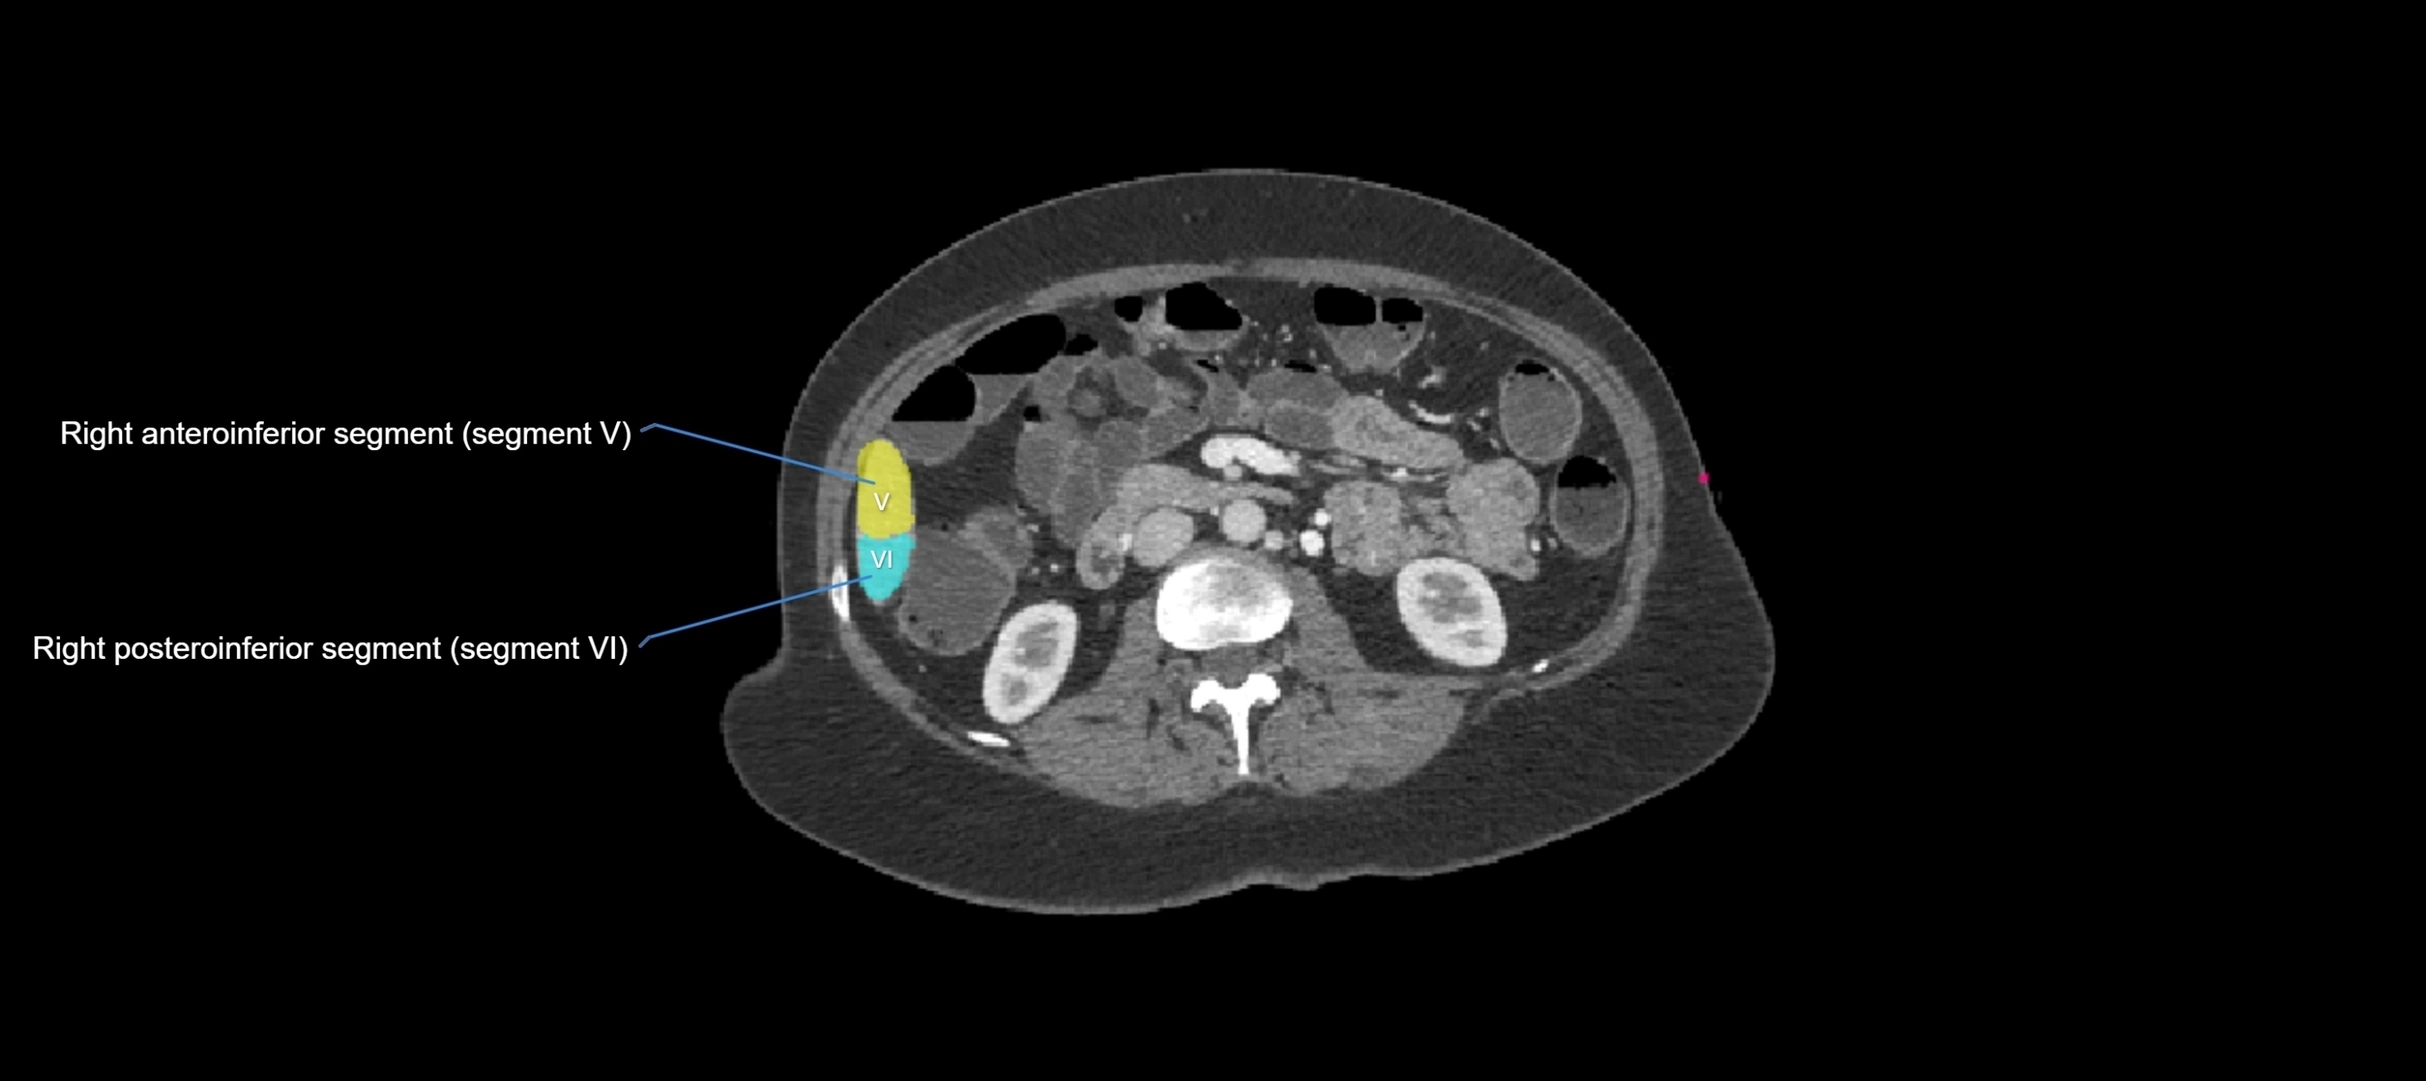

TEST YOURSELF

Fullscreen Image